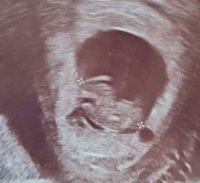

Her var jeg 9 uker i forrige svangerskap. Man kan se en liten bamsemums med hjerteslag. Men så veldig mye mer et par uker senere..